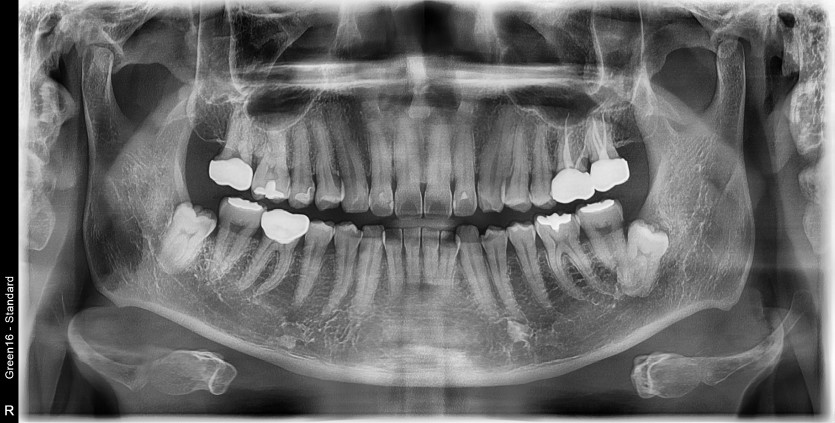

#38 사랑니 발치

구강외과 전문의가 당일발치했습니다.